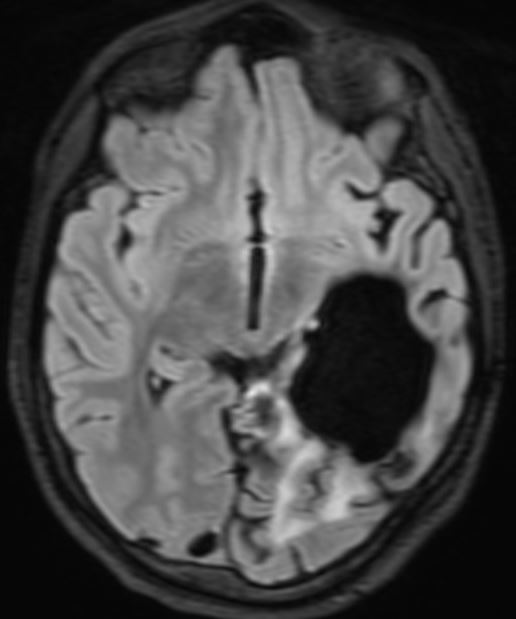

The patient presented with headache and vomiting and subsequently had surgery on three occasions for an intraventricular meningioma, with the following sequelae on MRI scan